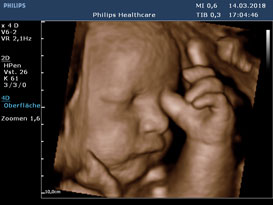

- 3D/4D-Ultraschallgeräte der neuesten Generation